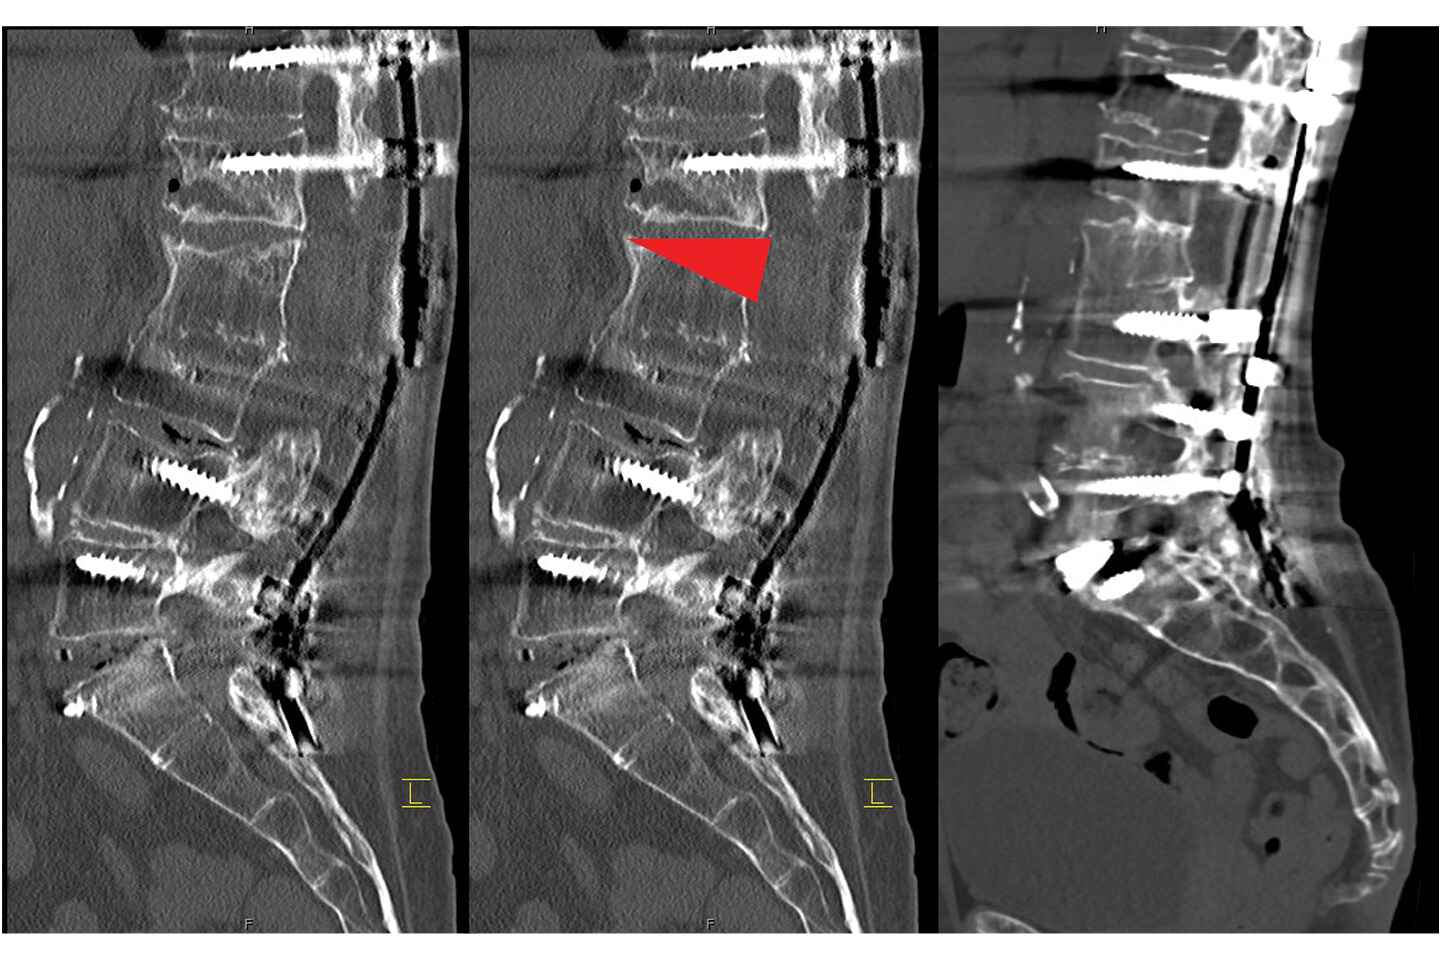

Intraoperative X-rays of the failed L5-S1 anterior lumbar interbody fusion. Source: NYU Langone Health

X-rays showing the location of the L2 pedicle subtraction osteotomy (indicated by the red arrow). Source: NYU Langone Health